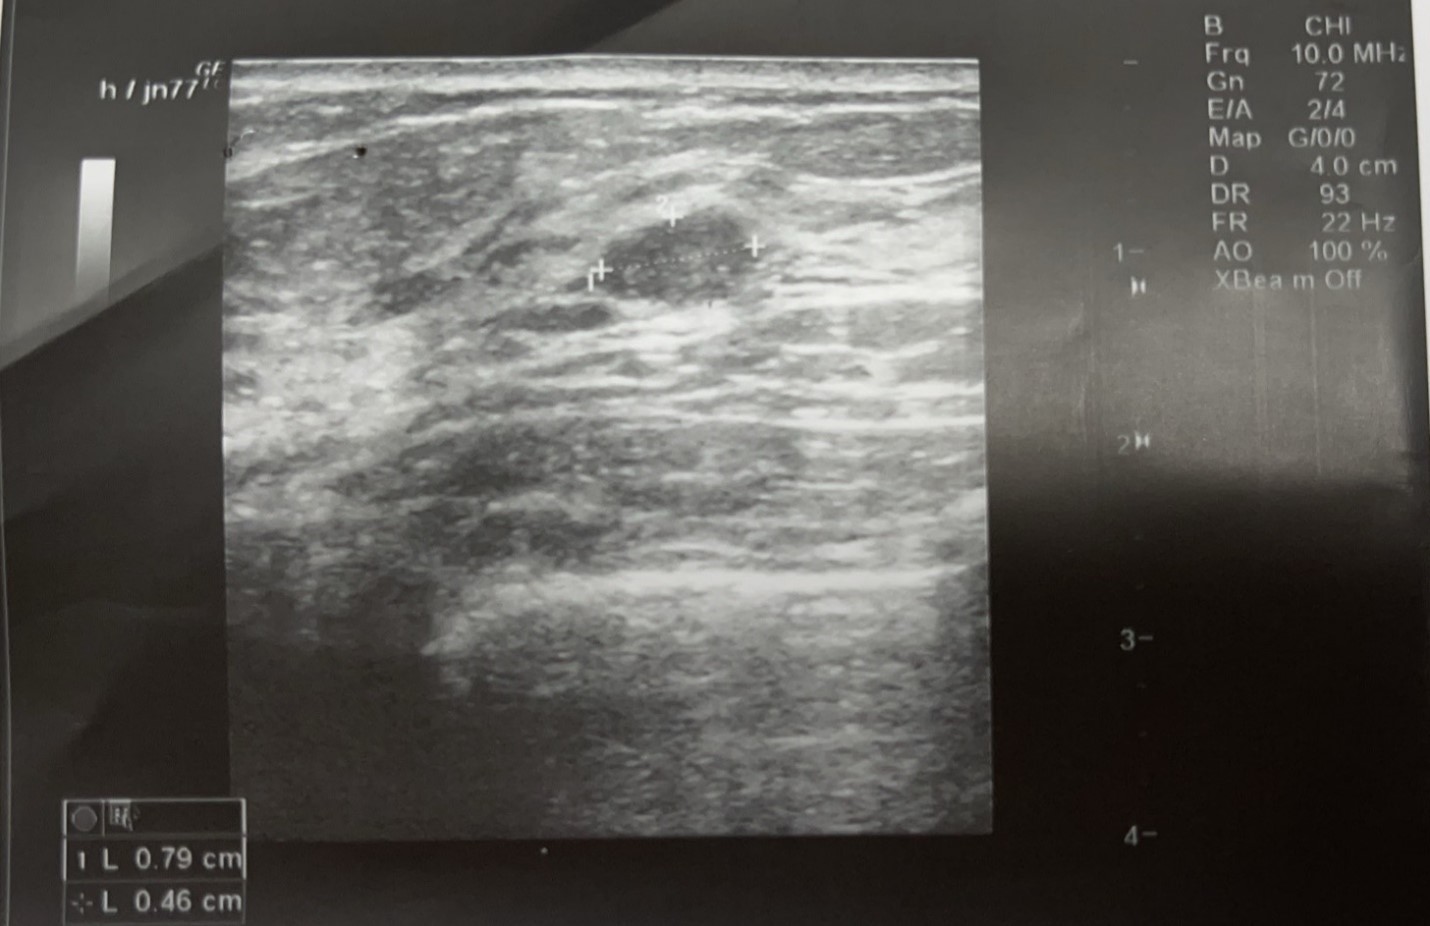

- Siêu âm vú là xét nghiệm thường quy, giúp đánh giá chính xác hơn về kích thước, bản chất những khối u hoặc hạch kích thước nhỏ, có thể bị bỏ sót khi thăm khám bằng tay. Đây là xét nghiệm có chi phí rẻ, dễ thực hiện, nhanh có kết quả.

Hình minh họa: tổn thương u vú phát hiện thấy trên siêu âm tuyến vú